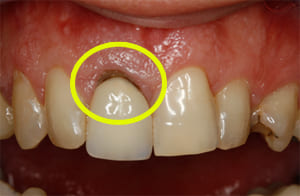

Thank you to our patients that have allowed us to show examples of our work

Have a look at just some of the many patient examples we have captured from BEFORE and AFTER their treatments and cosmetic surgeries.

From Whitening to Veneers, Fillings to Cosmetic Teeth Makeovers, here are some examples of the work that Dr. Dadabhai has provided to his patients to give them a more confident smile and a positive, pain free feeling.

Much of the work we carry out is to relieve pain and of course maintain the health of your teeth and gums, but many of our patients now ask for Cosmetic work to give them a more confident smile.

Cosmetic support has improved hugely over the last few years. Book a Consultation with Dr Dadabhai and he will prescribe a course of treatment to complete your perfect SMILE transformation.